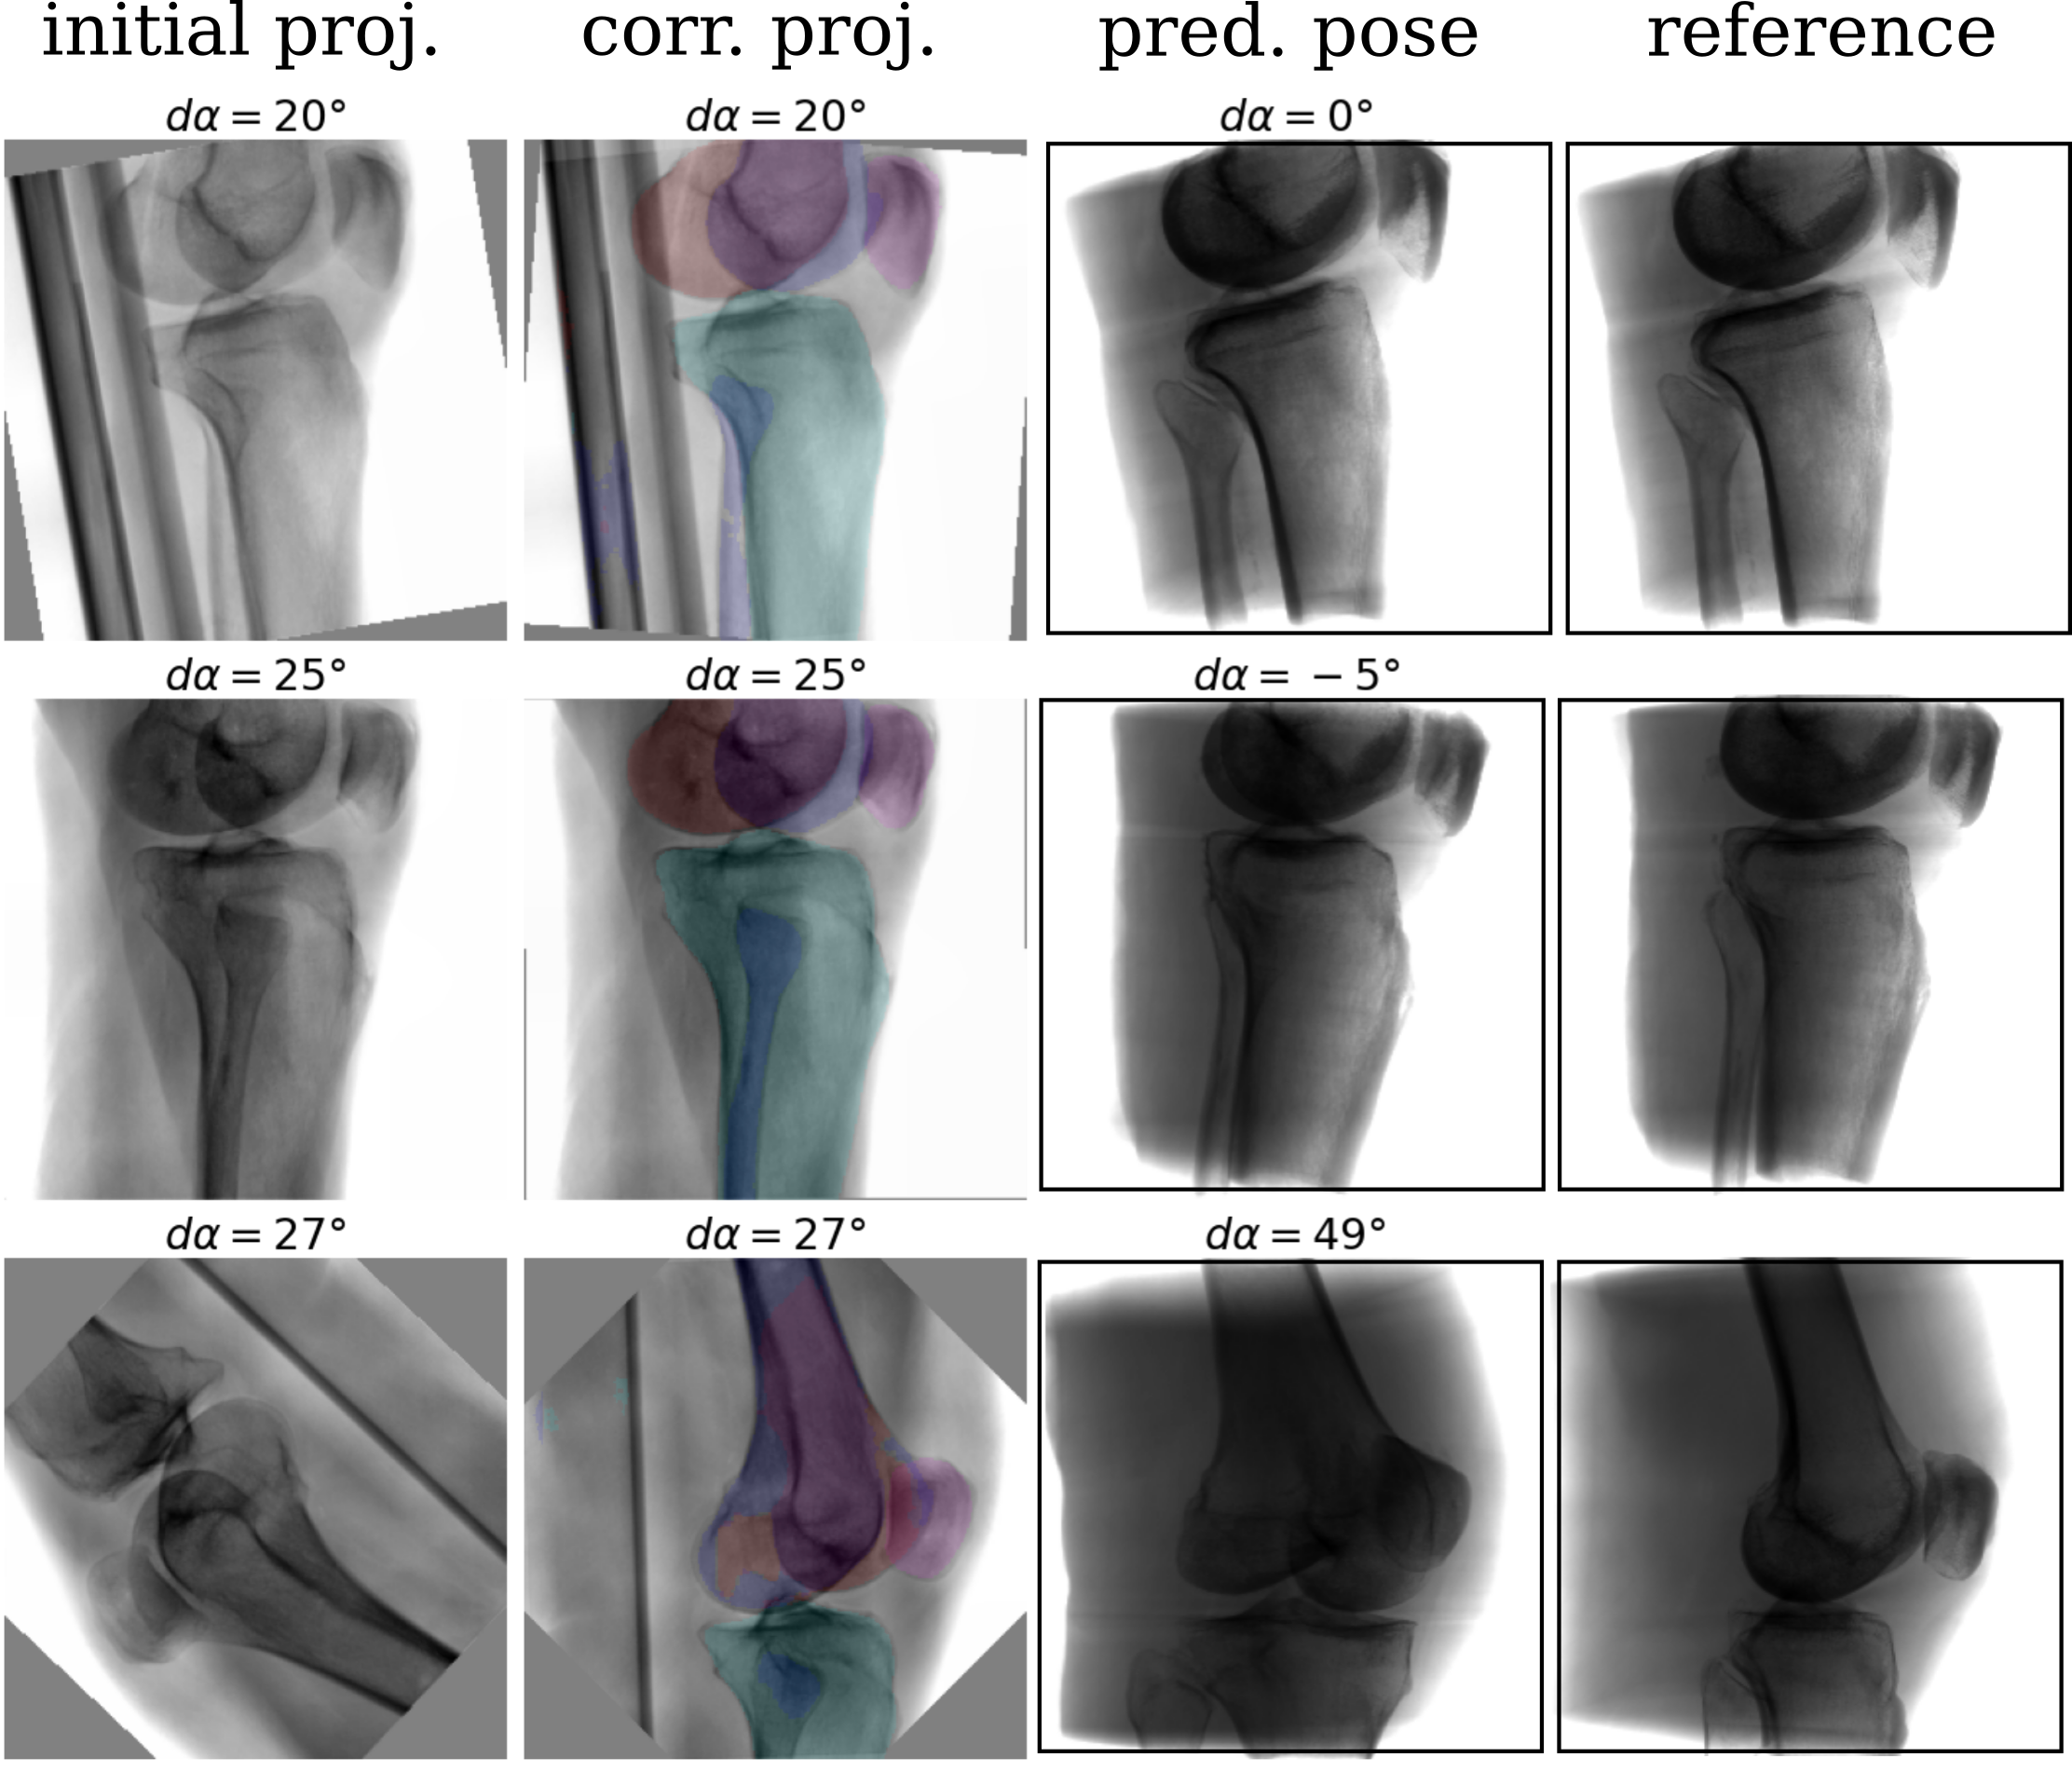

In an ablation study, the proposed shape-based view-independent pose regression was compared to view-specific direct intensity-based pose regression [11]. Further, the complete pipeline (2-step) is compared to a 1-step segmentation-based approach trained view-specific and view-independent (Fig. 4). Evaluation was performed on the simulated test DRRs and cadaveric X-rays (Fig. 5).

View-independent vs. view-specific networks: While the view-specific networks perform significantly better (lateral) or comparable (a.-p.) on the simulated data, the view-independent networks perform significantly better (a.-p.) or comparable (lateral) on the real data.

1-step vs. 2-step: The proposed 2-step approach performs significantly better or comparable than a 1-step shape-based pose regression approach on most validation cases (8/12) in viewing direction . Regarding the rotation, the 2-step approach improves performance across all validation cases.

Generalization from DRR to X-ray: The shape-based pose regression network combined with joint view-independent training clearly boosts the performance compared to direct intensity-based pose regression from to .

A complete framework for automatic acquisition of standard views of the knee is proposed that can handle several standard views simultaneously. The complete pipeline is trained on simulated data with automatically generated annotations and evaluated on real intraoperative X-rays. To bridge the domain gap, different augmentation strategies are suggested that address intraoperative confounding factors, e.g., the OR table. View-independent training and multi-label shape features improve the generalization from simulated training to real X-rays and outperform direct intensity-based approaches. View-independent networks result in more training data which showed to improve the generalization from simulated training to real X-rays. The 2-step approach increases robustness and simultaneously automates necessary preprocessing tasks like laterality and standard view recognition, which can be performed with very high accuracy on simulated (, ) and real data (, ). The approach is fast and easy to translate into the operating room as it does not require any additional technical equipment. Assuming that the surgeon acquires the initial X-ray with a pose offset within the capture range of , it has the potential to reduce time and unnecessary radiation during manual C-arm positioning. Furthermore, the segmentation features can serve as a sanity check and indicate the reliability of the pose regression result. Further experiments with a larger training set covering more anatomical variation, e.g., patella baja and different flexion angles [13], can potentially address observed failure cases.